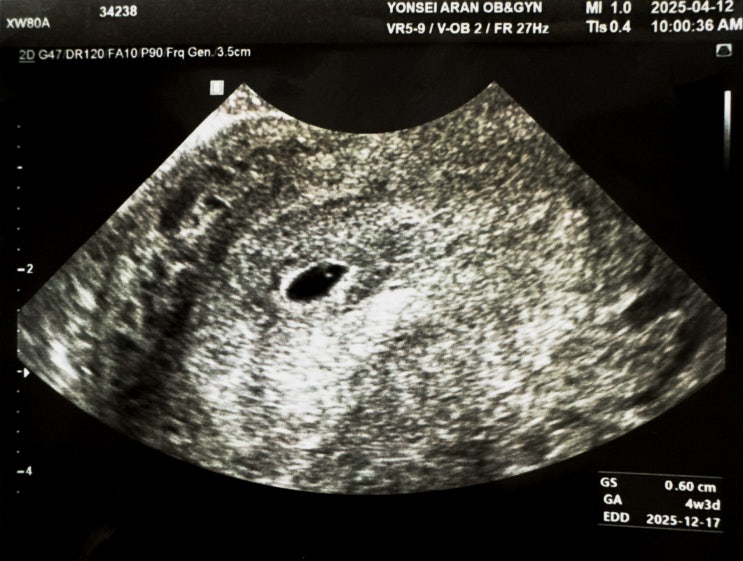

[둘째임신초기] 6주차 | 7주차 | 8주차 | 9주차 | 10주차 | 첫째와다른임신증상 | 입덧 | 보건소 임산부등록 | 보건소 산전검사

약처방으로 인해 매주 병원에 다니는 1인 장점은 매주 아기를 볼 수 있다는거 단점은 바우처를 너무 빨리 ...

[둘째임신초기] 임신성공 | 5주차 | 크녹산 | 유산방지 | 유산위험산모 | 씬지로이드정

2025.04.12 토요일 남편이랑 병원에 다녀왔습니다. 증상이 거의 없던 터라 조금 걱정은 되었으나, 임테기 2...